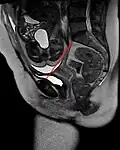

![]() The pelvic inlet (shown in red) | |

The pelvic inlet or superior aperture of the pelvis is a planar surface which defines the boundary between the pelvic cavity and the abdominal cavity (or, according to some authors, between two parts of the pelvic cavity, called lesser pelvis and greater pelvis). It is a major target of measurements of pelvimetry.

Its position and orientation relative to the skeleton of the pelvis is anatomically defined by its edge, the pelvic brim. The pelvic brim is an approximately apple-shaped line passing through the prominence of the sacrum, the arcuate and pectineal lines, and the upper margin of the pubic symphysis.